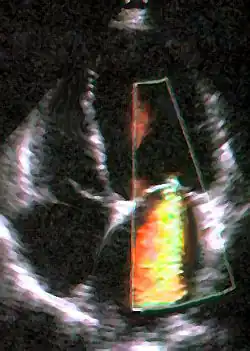

An echocardiogram is commonly used to confirm the diagnosis of MR.[16] Color doppler flow on the transthoracic echocardiogram (TTE) will reveal a jet of blood flowing from the left ventricle into the left atrium during ventricular systole. Also, it may detect a dilated left atrium and ventricle and decreased left ventricular function.[6] A transesophageal echocardiogram can give clearer images if needed as the back of the heart can also be viewed.[17]

where Vmitral and Vaortic are, respectively, the volumes of blood that flow forward through the mitral valve and aortic valve during a cardiac cycle. Methods that have been used to assess the regurgitant fraction in mitral regurgitation include echocardiography, cardiac catheterization, fast CT scan, and cardiac MRI.The echocardiographic technique to measure the regurgitant fraction is to determine the forward flow through the mitral valve (from the left atrium to the left ventricle) during ventricular diastole, and comparing it with the flow out of the left ventricle through the aortic valve in ventricular systole. This method assumes that the aortic valve does not have aortic insufficiency.Another way to quantify the degree of MR is to determine the area of the regurgitant flow at the level of the valve. This is known as the regurgitant orifice area and correlates with the size of the defect in the mitral valve. One particular echocardiographic technique used to measure the orifice area is measurement of the proximal isovelocity surface area (PISA). The flaw of using PISA to determine the mitral valve regurgitant orifice area is that it measures the flow at one moment in time in the cardiac cycle, which may not reflect the average performance of the regurgitant jet.